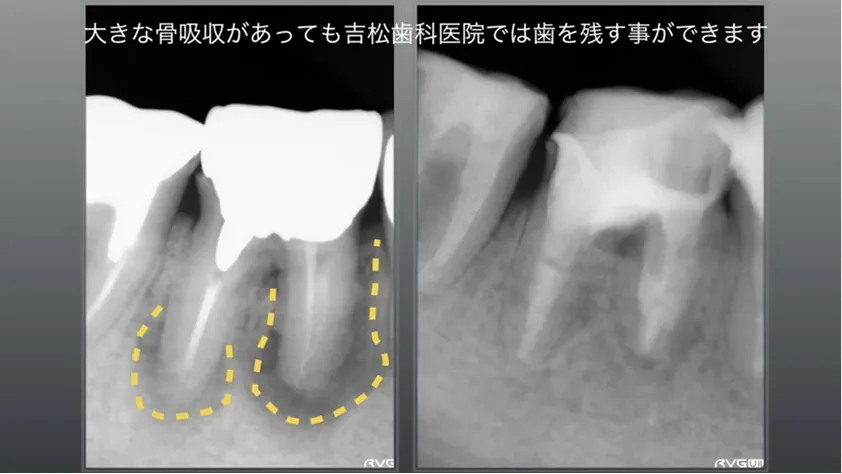

大きく骨吸収しているが、治療後骨再生が確認できます